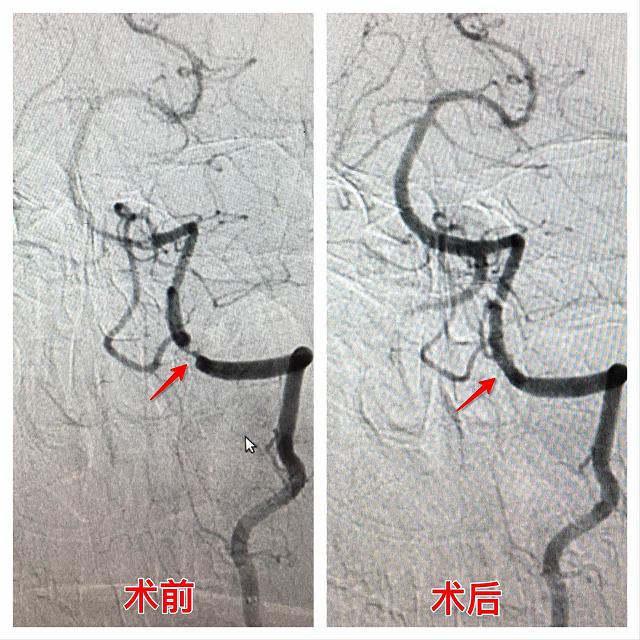

患者谢某,男性,76岁,因反复头昏伴眩晕来我院作颈部B超检查提示颈内动脉起始部动脉粥样斑块形成,收住入院后经过我院DSA检查明确诊断为:1、双侧椎动脉V4段重度狭窄;2、左侧颈内动脉起始部狭窄(约50%);3、右侧颈内动脉起始部狭窄(约75%);4、脑梗塞。高博士及我院神经介入团队详细分析病情,DSA显示供应大脑血液的四根血管均有不同程度狭窄,病情复杂治疗难度大,考虑患者反复头昏伴眩晕与双侧椎动狭窄后循环缺血有直接关系,本次手术方案主要先解决双侧椎动脉狭窄以满足后循环血供从而缓解头昏目眩症状,对于双侧颈内动脉起始部狭窄亦需要后期服药定期复查,必要时仍需支架植入处理,可行性方案很快确定并得到了患者及家属的同意,采取在局麻下行“双侧椎动动脉狭窄支架植入术”,术中由于血管多处迂曲采用了同轴技术将8FGuiding+5FNavia置入右侧椎动脉V3段,通过0.014 BMW导丝将Apollo 2.5-8mm球扩支架在6个大气压下进行扩张并释放,复查造影显示远端及狭窄处血流明显改善,同样方法将Apollo 2.5-13mm球扩支架在6个大气压下于左侧椎动脉狭窄处进行扩张并释放,过程虽然艰难但手术非常顺利,术后患者头昏眩晕症状得到明显改善,3天后痊愈出院。

右侧椎动脉

左侧椎动脉